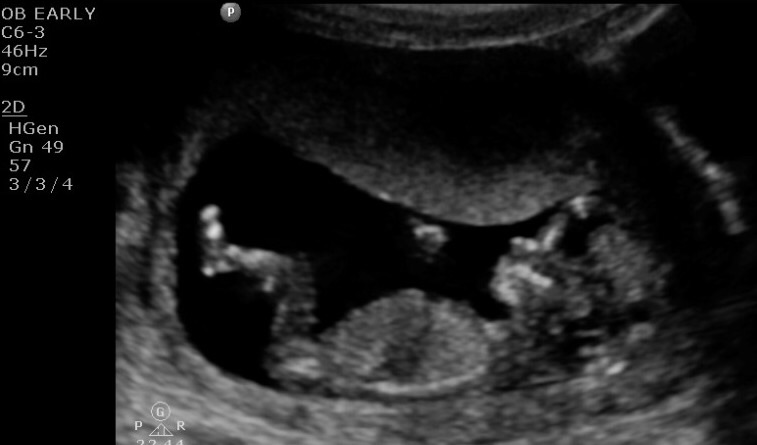

Here's our little love at 12 weeks! I can't get over how much he/she already looks like a 'real' person, can't wait for the next US when we find out the sex! So excited